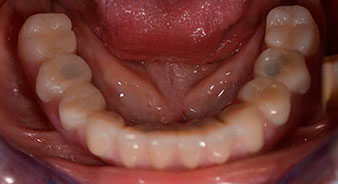

След изчакване на необходимото време за осеоинтеграция, финалният отпечатък на имплантите е свален и следователно е изработена финалната протеза (Фиг. 19 и 20). В този момент, лекарят по дентална медицина и пациентът могат да обсъдят дали да използват керамични или пластмасови фасети и циркониева или метална рамка. В този случай, екипът на д-р Паску избира пластмасови фасети, имайки предвид неясната прогноза относно частичното обеззъбяване в челюстта и фактът, че зъб 24 е прорастнал. Този вид протеза обикновено е по-лесна за адаптиране и впоследствие може да бъде променяна спрямо новата ситуация в челюстта.

Осеоинтеграция

Фиг. 19

Импланти

Фиг. 20